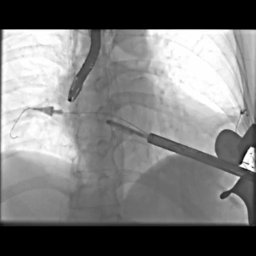

手术过程造影

手术在厦心杂交手术室进行,患者处于全麻状态,在实时三维食道超声的指引下,心外科在患者左胸前切开4-5cm的切口,经心尖预缝荷包区域导入AMEND成形环植入系统,顺利通过二尖瓣结构中央区域进入左心房后,在体外操作AMEND系统将“D”型成型环在主动脉瓣与二尖瓣间极为狭小的空间内精确释放,并先后铆钉二尖瓣环的后叶及前叶,从而达到缩小二尖瓣环的目的(图2),这一步操作要求非常精准,稍有不慎便会损伤周围组织,引起并发症。术后即刻,患者二尖瓣反流明显减轻,达到轻度水平(图3),手术从麻醉到结束平均历时3个小时。